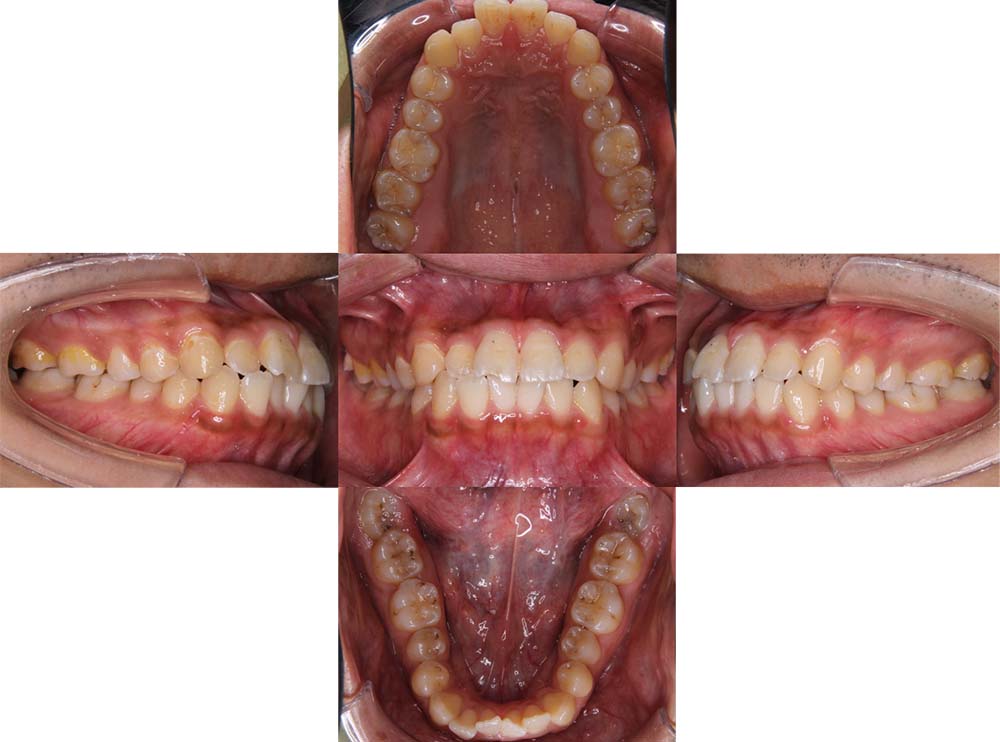

症例01

| 主訴 | 歯並びがガタガタしている。 |

| 診断名あるいは主な症状 | 叢生 |

| 年齢/性別 | 22歳・男性 |

| 矯正ステージ | 大人の矯正治療 |

| 治療方法 | ワイヤー矯正 |

| 抜歯部位/抜歯有無 | 非抜歯 |

| 治療内容 | 上顎大臼歯の遠心移動により前歯のガタガタを排列スペースを獲得し全顎的な排列を行った。 |

| 費用 | 85万円程度(2025.10時点の料金となります。) ※矯正基本料金、審美ブラケットを含む |

| 治療期間 | 2年4ヶ月 |

| 主なリスク・副作用 | 痛み、歯根吸収、歯肉退縮、虫歯、後戻り |